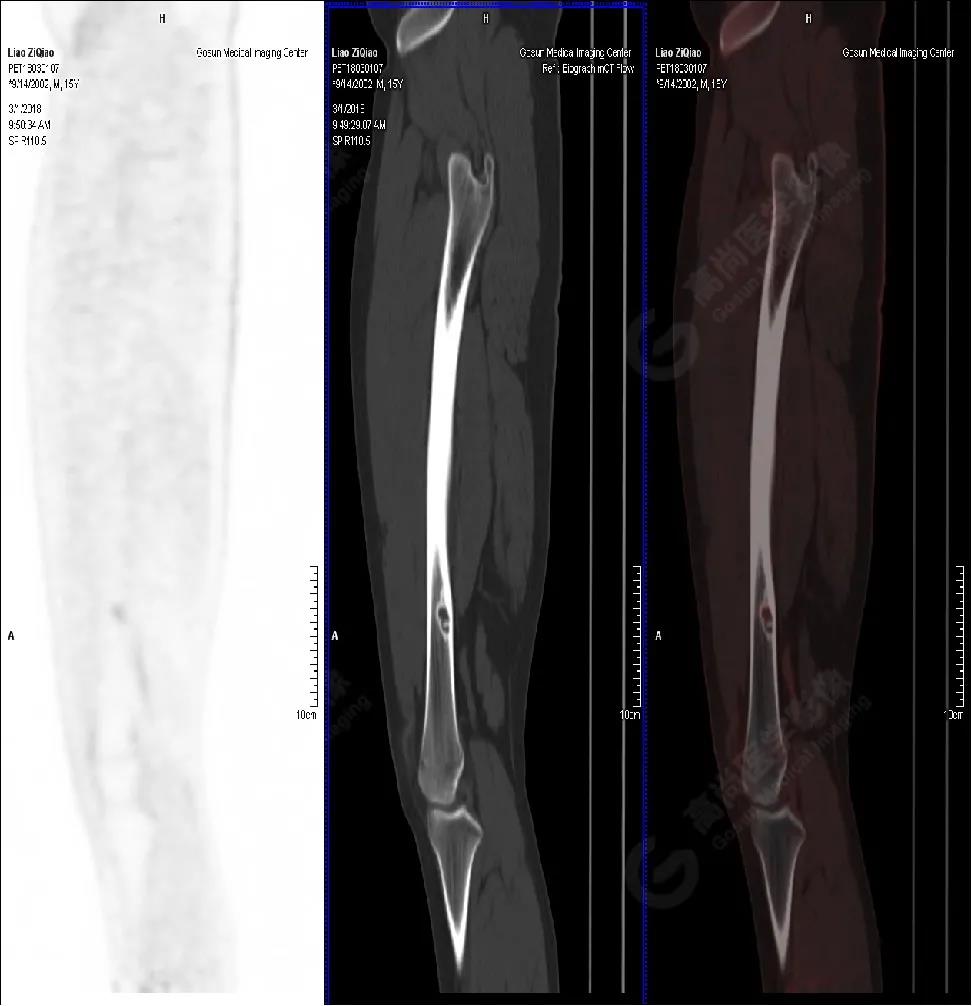

男性,15歲,右側大腿疼痛1月余,DR提示右側股骨下段囊性低密度占位。既往無外傷史、否認肝炎、結核及手術史。

右側股骨下段(內(nèi)側緣)見骨皮質(zhì)局限性膨脹性破壞,突入髓腔內(nèi),邊界清楚,邊緣硬化,灶內(nèi)見纖維骨嵴,放射性攝取略增高,SUV最大值為1.4,平均值為1.3。

右側脛骨良性骨病,以非骨化性纖維瘤可能性大。

隨訪結果:活檢病理確診非骨化性纖維瘤。